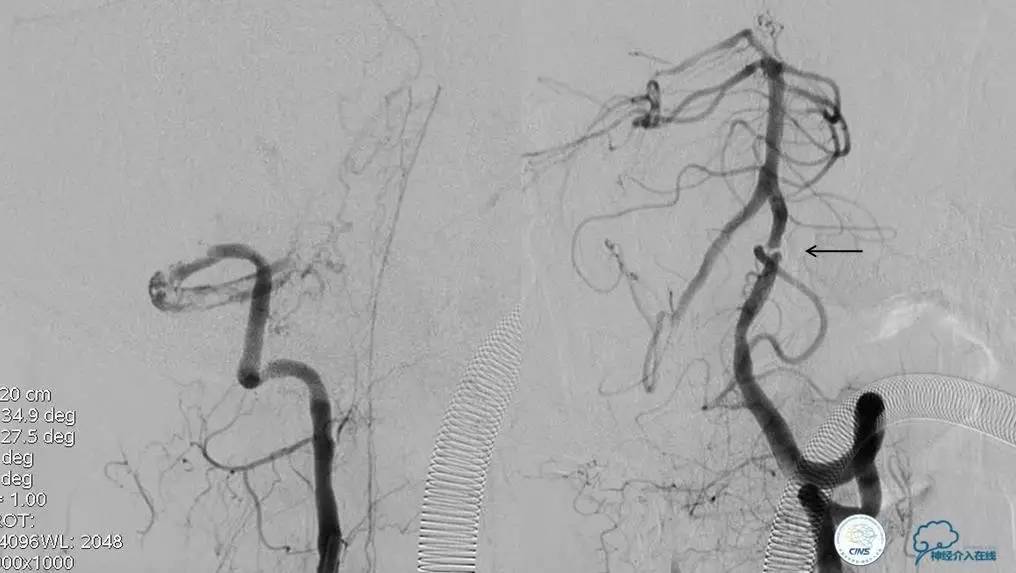

▼开通

▼术前DSA

▼术中DSA

▼术后DSA

再通技术简要步骤

1.微导丝探查、穿过闭塞段(轻柔!)

2.微导管过闭塞段后必须造影确认在血管真腔

3.交换微导丝,撤出微导管

4.球囊预扩(原则:缓慢充盈,从小到大)

5.支架成形(保证系统稳定)

注:释放支架前及术后3天严格控制收缩压<120mmHg